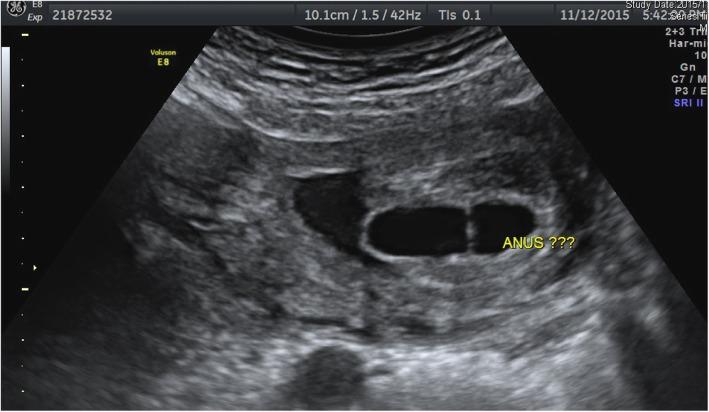

We present a case of congenital megalourethra, diagnosed prenatally at 22 weeks' gestation, in which the penis appeared severe dilated with complete absence of the corpora spongiosa and cavernosa. This case also revealed absence of perianal muscle which was in associated with imperforate anus. Detailed prenatal ultrasonographic findings predicted the high possibility of poor outcome of the fetus in the pulmonary, renal, and sexual functions.

This case serves to identify not only the marked bilateral hydronephrosis features but also the striking lower urethral malformation with obstruction flow effect of the penis. Indeed we believe this is the first case report of a rare case of fetal megalourethra associated with imperforate anus at early second trimester on ultrasonography imaging.

我们报告了一例先天性巨尿道病例,该病例在 22 孕周时被产前超声诊断,其阴茎严重扩张,海绵体和阴茎海绵体完全缺失。该病例还显示了肛门周围肌肉缺失,与先天性肛门闭锁有关。详细的产前超声检查结果预测了胎儿在肺部、肾脏和性功能方面不良结局的可能性较高。

本病例不仅可以识别明显的双侧肾积水特征,还可以发现明显的下尿道畸形伴阴茎梗阻性流态。事实上,我们相信这是首例在妊娠中期超声图像上显示罕见的胎儿巨尿道伴先天性肛门闭锁的病例报告。